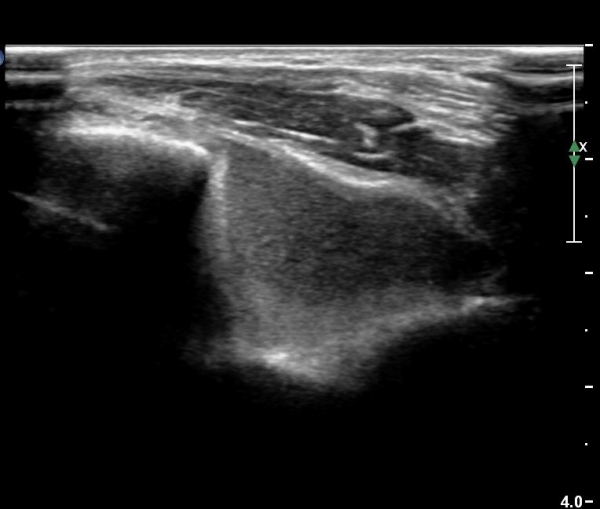

ÁÖµÎ¿Í Á¾´Ü¸é°Ë»ç¿Í Ⱦ´Ü¸é°Ë»ç¿¡¼­ ÁֵοͿ¡ ÀÌÁúÀû¿¡ÄÚ¸¦ º¸ÀÌ´Â

´Ù·®ÀÇ ¼ö¾×Àú·ù°¡ °üÂûµÊ(»çÁø 5, 6).

ÃÊÀ½ÆÄ°Ë»ç¿¡¼­ ÀÌÁúÀûÀÎ °í¿¡ÄÚ ¼ö¾×Àú·ù´Â ÀüÇüÀûÀÎ ±Þ¼º °üÀý³» ÃâÇ÷ ¼Ò°ßÀÌ´Ù.

ÀÌ·± ¼Ò°ßÀ» º¸ÀÌ´Â °æ¿ì¿¡´Â °üÀý³» °ñÀýÀ» ÀǽÉÇÏ°í °ñÀý È£¹ß ºÎÀ§¸¦ ¼¼½ÉÇÏ°Ô °Ë»çÇØ¾ß

Çϴµ¥ ÆÈ²ÞÄ¡¿¡¼­´Â ¿ä°ñµÎ, ¼ÒµÎ, ±¸»óµ¹±â(coronoid process), ÁÖµÎ, ³»»ç°ú, ¿Ü»ó°ú¸¦

öÀúÈ÷ È®ÀÎÇØ¾ß ÇÑ´Ù.